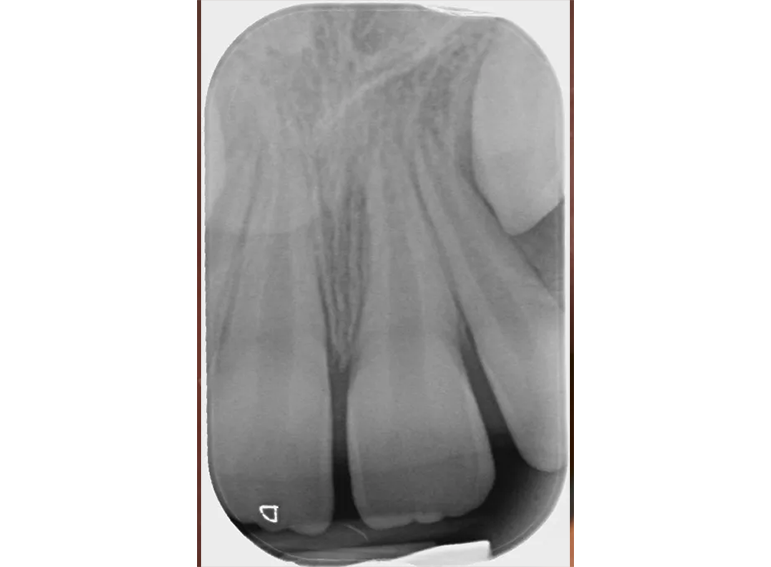

Root filling of an immature tooth and bleaching.